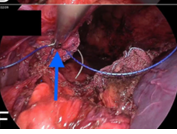

Congenital diaphragmatic hernia (CDH) is a birth defect involving improper formation of the diaphragm, leading to the protrusion of abdominal organs into the chest cavity. The CDH is classified depending on the location of the defect as postero-lateral, central and anterior. Depending on the side, it is classified as right, left and bilateral. A majority of CDH defects are postero-lateral defects and are commonly referred to as Bochdalek hernias (BH). Herein, the authors present the case of a 29 years old male patient diagnosed with a large left recurrent Bochdalek hernia. He was operated for it in another hospital by another surgeon 5 months back. That previous surgical intervention was initially planned via laparoscopy. But, intraoperatively, it had to be converted to open surgery due to technical difficulty. Post the first surgery, after about 1.5 months, he started developing pain in the back of his left chest. However, due to financial constraints, he did not seek any consultation with anyone at that time. The authors successfully performed a laparoscopic repair of this difficult condition. The rationale for reporting this case is to underscore the relative ease of a laparoscopic over open surgical intervention, on the ‘roof’ of the abdomen and also the lower chest. Also, it hopes to highlight that laparoscopic repair of BH is feasible even in challenging, difficult and recurrent scenarios, in an advanced setup backed up by the requisite surgical expertise.